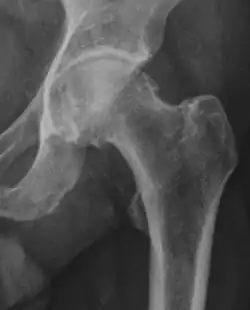

Projectional radiography ("X-ray") is often considered first line for FAI.[10] Anterior-posterior pelvis and a lateral image of the hip in question should be attained.[10] A 45-degree Dunn view is also recommended.[10][19]

Degree of bulging of the femoral head-neck junction: In normal conditions there is a symmetric concave contour at the junction of the femoral head and neck. Loss of this concavity or bone bulging may lead to cam type impingement. The degree of this deformity can be measured by the alpha angle. Although it can be measured in the cross-lateral view, the 45° Dunn view is considered more sensitive and the frog leg view more specific in determining pathologic values. |

|